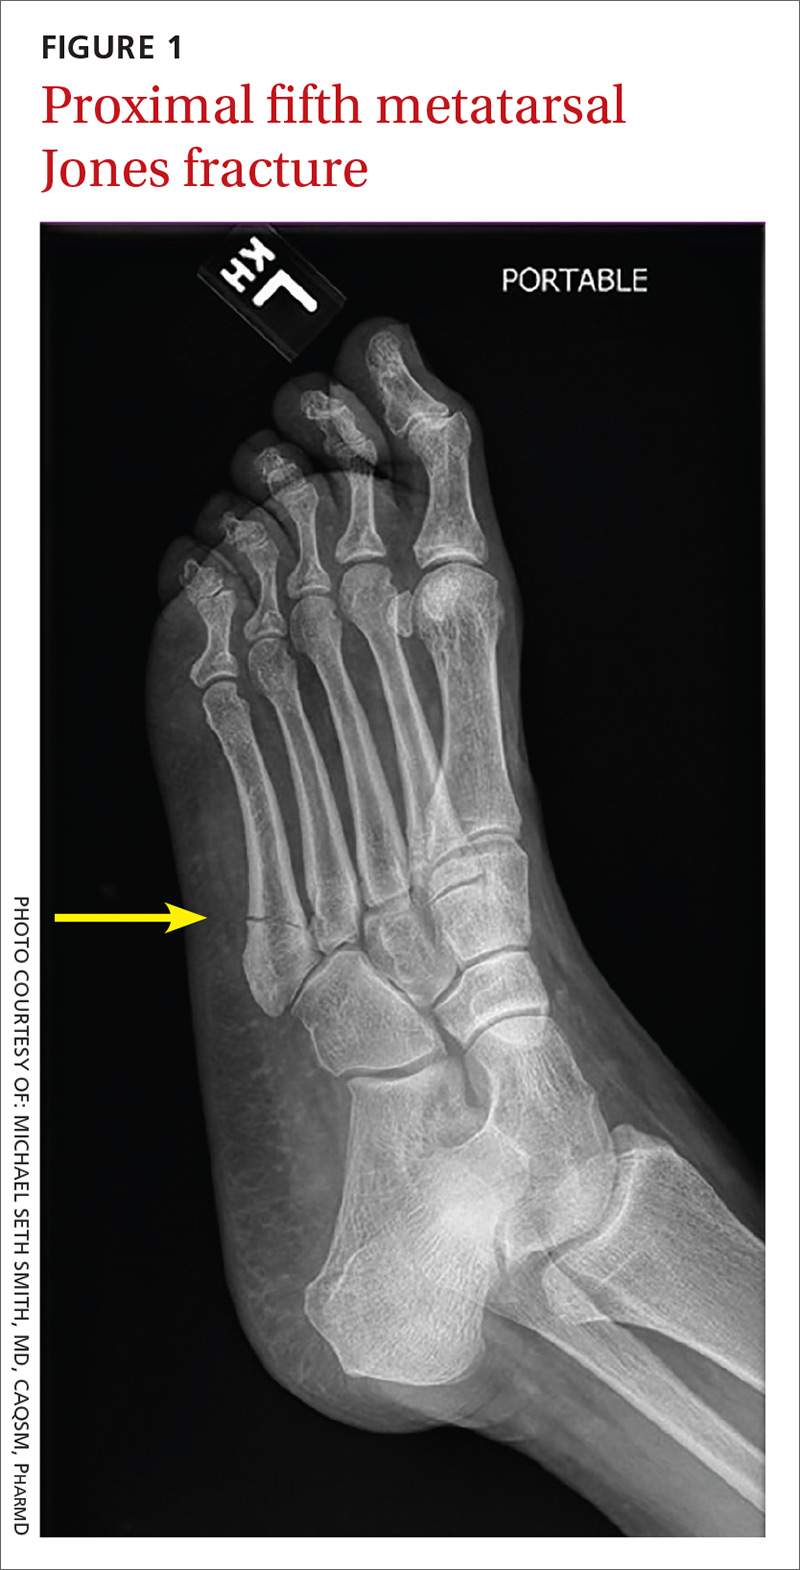

From www.aafp.org

Diagnosis and Management of Common Foot Fractures AAFP Fracture In Bottom Of Foot  Symptoms include pain, swelling, redness, bruising, and limping on the affected foot. They're caused by repetitive force, often from overuse — such as repeatedly jumping up and down or running long distances. A lisfranc fracture is a type of broken foot. Broken bones in the foot are a common injury. Traumatic injuries — like accidents and. A broken foot, or. Fracture In Bottom Of Foot.

From www.mdedge.com

Adult foot fractures A guide MDedge Family Medicine Fracture In Bottom Of Foot  Stress fractures are tiny cracks in a bone. The lisfranc joint is the spot on top of your foot where the metatarsal. They're caused by repetitive force, often from overuse — such as repeatedly jumping up and down or running long distances. Pain that gets better during rest. A broken foot, or foot fracture, is a common injury that can. Fracture In Bottom Of Foot.